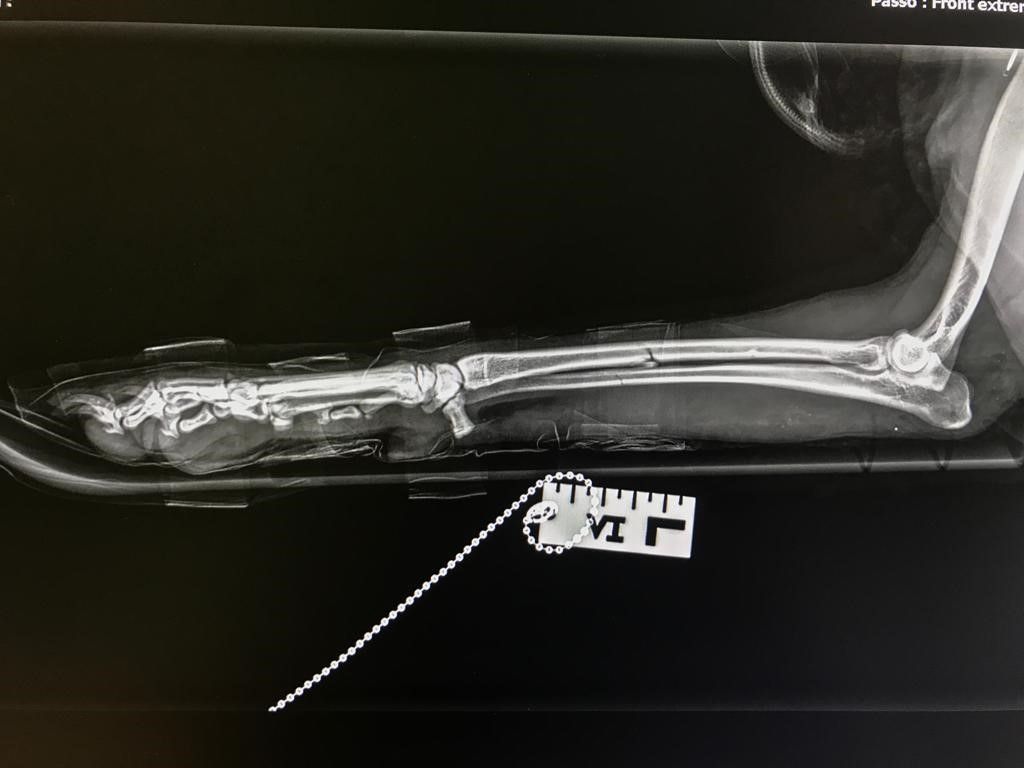

Per offrire cure sempre più efficaci e sicure, la struttura si avvale di tecnologie di ultima generazione. Un nuovo apparecchio radiografico digitale diretto consente diagnosi rapide e dettagliate, migliorando l’accuratezza delle valutazioni cliniche. Inoltre, la collaborazione con un chirurgo esperto e l’impiego di strumentazione chirurgica all’avanguardia permettono di eseguire interventi con maggiore precisione, sicurezza e rapidità. Tra questi, la sterilizzazione e altre procedure chirurgiche risultano notevolmente agevolate, garantendo il massimo benessere per il paziente e un recupero più rapido.